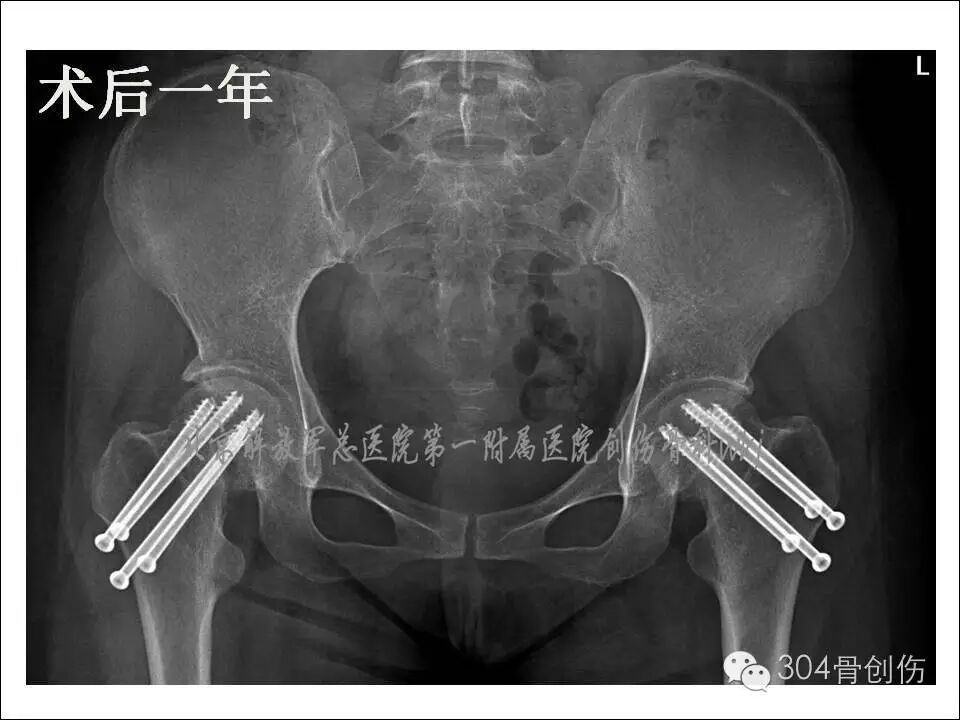

全麻下双侧股骨颈骨折闭合复位内固定。在C型臂透视下,牵引床辅助闭合复位,固定股骨头、下肢极度内旋,骨折复位满意,为增加固定强度,双侧各经皮打入4枚空心螺钉(图)。术后口服钙尔奇600mg每天2次,骨化三醇胶丸0.25ug 每天3次。双腿非负重活动。

术后6个月患髋部X线显示,股骨颈有短缩,螺钉少许退钉,骨折基本愈合,骨折愈合左侧优于右侧。术后1年,股骨颈未继续缩短,左侧股骨颈完全愈合,右侧股骨颈略差,行走时右髋偶感不适。术后2年随访时(图),双侧股骨颈骨折愈合,患者步态正常(图)。

图-术后X线片